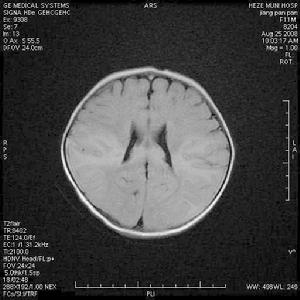

肉眼所見大腦充血水種,並有廣泛的神經細胞變性,腦組織多處有出血灶。顯微鏡檢查見神經細胞變性壞死血管周圍有淋巴細胞、單核細胞和多形核白細胞浸潤形成“血管周圍套”有的膠質細胞增生和多形核白細胞堆積形成結節。病灶主要見於大腦基底節,腦幹灰質和白質也可侵犯小腦和脊髓。